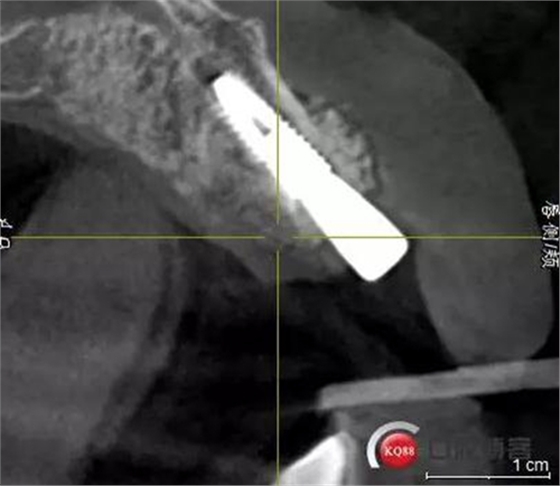

患者:王XX 年齡:42 上前牙松動數(shù)年,從未做過任何處理,今來院就診;檢查:CBCT示上前牙區(qū)顎側(cè)一大小約7x7mm囊腫;治療計劃:即刻種植同期摘除囊腫

術前CBCT